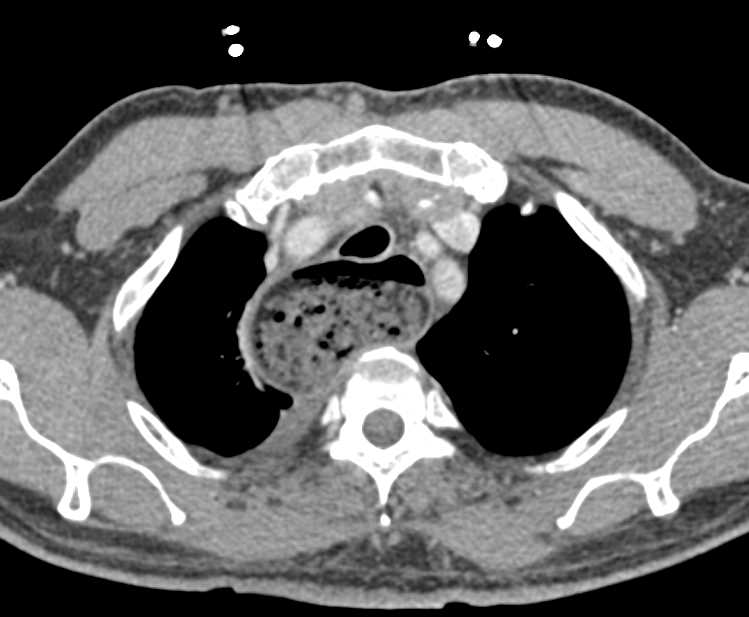

Esophageal Cancer